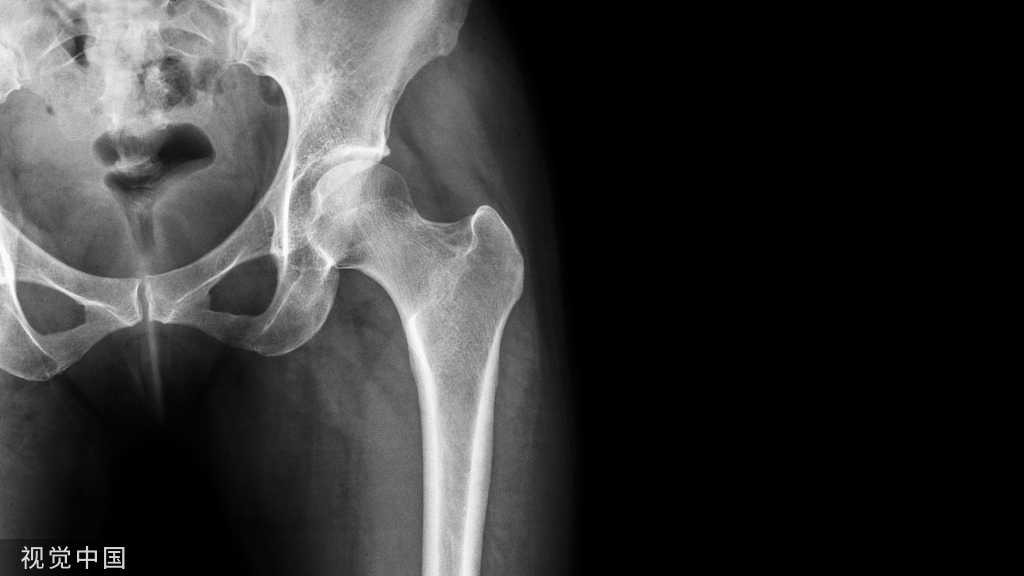

本病的潜伏期为伤后4小时至数天,平均时间为46小时,临床表现分为主要症状和次要症状。主要症状为呼吸功能障碍、脑症状及皮下出血点。次要症状包括发热、心动过速,视网膜改变、黄疸及肾功能障碍。最常见的病因是20~30岁病人的长骨骨折,一般为胫骨及股骨骨折。在60岁以上的病人,髋部骨折也常引起此综合征。

约有25%的病人会在伤后12小时内出现症状,75%的病人在36小时内出现症状。有许多症状轻微的病例被漏诊。有研究表明,60%~70%骨髂损伤的病人会出现不同程度的低氧血症。发病率最高的是胫骨或股骨干骨折,或是同时有胫骨及股骨干骨折者,其次是髋部骨折,动脉氧分压常下降到60 ~70mmHg。